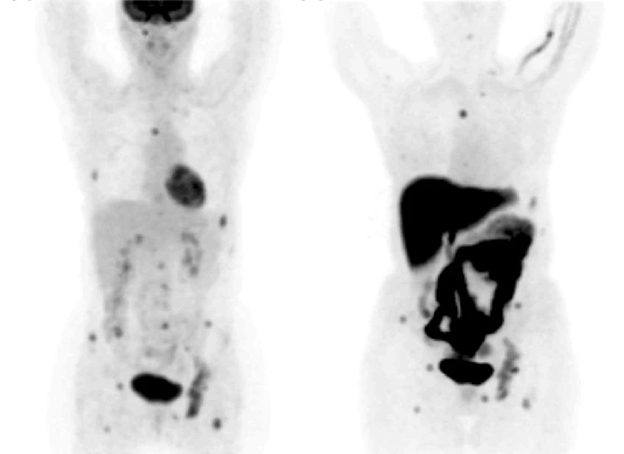

To further increase the specificity and sensitivity of PET, researchers suggested combining CT and PET. FDG-PET/CT is used to estimate the therapeutic response of the tumor, detect recurrence or distant metastasis, and detect tumors in the early stage. Additionally, FDG-PET/CT can locate metastasis in unexpected locations (28). A prospective evaluation conducted by Shawky et al. (28) found that PET/CT was able to detect contralateral lesions in two patients (Figure 2), which traditional CT imaging could not detect. Moreover, PET/CT imaging could detect lesions in the bone marrow which was not detected by CT imaging as well (28). Several studies have shown that PET/CT can detect additional lesions than those detected by CT, and it can detect unsuspected distant metastasis in just one whole body scan (29, 30). Bone metastasis is the most common site of breast cancer metastasis. Both CT and PET/CT can detect osteoblastic, osteoclastic, and mixed bone metastases with the same sensitivity and the same specificity (28). However, PET/CT can detect bone metastasis earlier than CT and can detect bone infiltration that cannot be seen with traditional CT imaging. Additionally, it can detect the resolution of bone infiltration before the appearance of definitive signs of healing (28).

Figure 2: Detection of contralateral breast cancer using PET/CT (28).